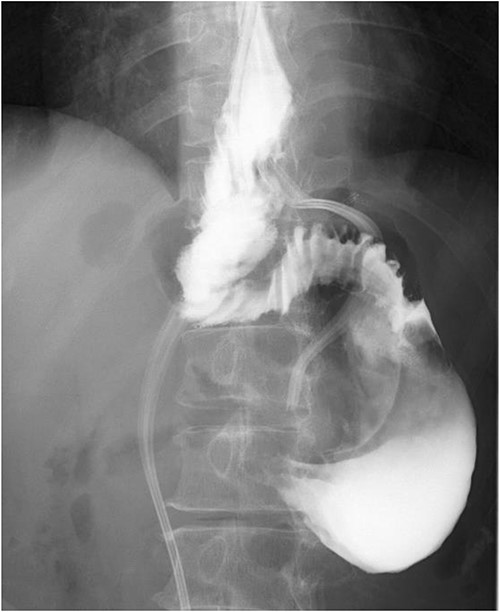

A 60-year-old female with dysphagia and vomiting visited the university hospital. In 2007, she underwent esophageal diverticulum resection (procedure unknown) with a diagnosis of an esophageal diverticulum, which subsequently recurred. In 2011, she underwent a transesophageal hiatus diverticulectomy and a fundoplication (Nissen procedure) at a local hospital. In 2013, dysphagia and vomiting appeared. The patient was diagnosed with recurrence and underwent balloon dilatation for follow-up. In 2015, the patient came to our hospital due to persistent symptoms. After one balloon dilation, the patient did not show any improvement and was referred for surgery. Esophageal fluoroscopy revealed a diverticulum 5 cm in size in the lower esophagus just above the eruption. There was no significant change in the diverticulum size before and after dilation (Figs 1 and 2). Gastrointestinal endoscopy revealed a diverticulum in the lower esophagus, with a residue accumulation (Fig. 3). The esophagus directly below the diverticulum was narrowed. The patient was diagnosed with recurrent lower esophageal diverticulum and underwent surgery.

Esophageal fluoroscopy (before dilation). There was a 5 cm-sized diverticulum in the lower esophagus just above the eruption.